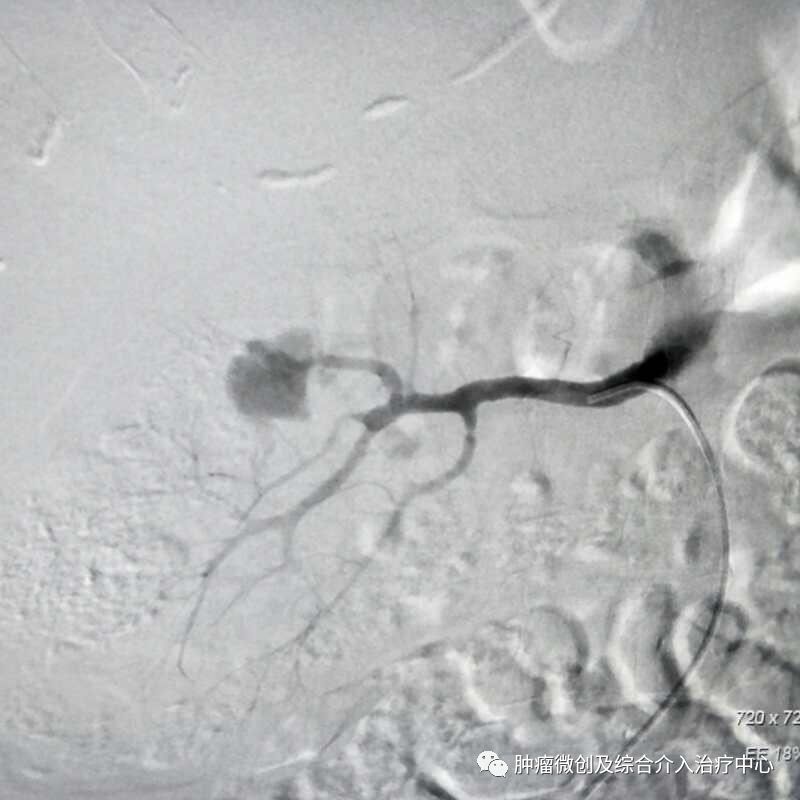

(介入栓塞术后提示无肾动脉出血肾动脉-栓塞成功)